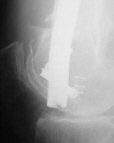

Attached are few examples from our Hospital:

A. Difficult reductions, even in retrograde nailing (my preference, easier control of "small" distal fragment) and it is much, much harder to do it anterograde (Alex, do you have one good case in your collection of anterograde nailing in very distal fractures - as you have suggested that I

should have done it in my previously posted case?

Malpositioning is much too common (recurvatum, varus - valgus).

B. Fixation loosening: distal cutting of the nail, non-unions do happen (cases attached).